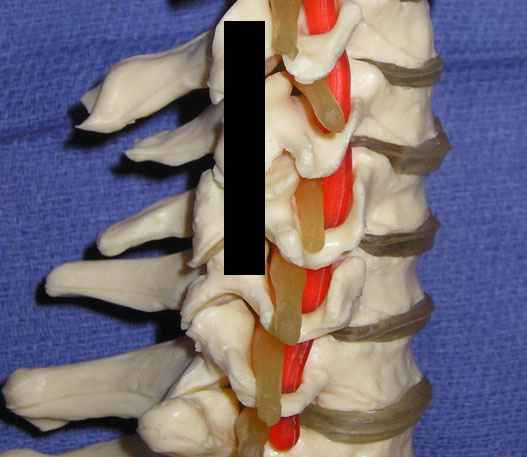

The lumbar facet joints, pedicles, lamina, supraspinous and intraspinous ligaments, and the spinous processes form the posterior column of the spine. The lumbar facet joints are synovial joints formed by the superior and inferior articular processes of each respective vertebral body. In the lumbar spine the superior articular facet is anterior and lateral to the inferior articular facet. Facet joint orientation varies with spinal level and with the development of degenerative spondylolisthesis. Each joint has fibrous joint capsule, a synovial membrane, and hyaline cartilage. Fat also exists within the intra-articular space, and fat in the subcapsular pocket is attached to the fat in the extracapsular area. The adipose tissue pads and fibro-adipose meniscoids act as a protective barrier similar to a meniscus in a knee joint.[24] At its thickest interval the cartilage is approximately 2 mm. The facet joint only holds a small volume, typically 1–2 mL. As we age, areas of the cartilage develop erosion and thinning.[25] The facets contribute 40% to torsional load resistance in the lumbar spine. The facet joints assist in resisting forward translation, rotation and compressive loads, and shearing forces generated in the lumbar spine. By resisting these movements they assist in the protection of the intervertebral disc.[26]

The innervation for the lumbar facet joints arises from the L1 to L4 medial branches of the dorsal rami and the L5 dorsal ramus. As a spinal nerve exits the neural foramen it divides into a ventral primary ramus and a dorsal primary ramus. The L1 through L4 dorsal rami divide consistently into two branches, medial and lateral. At times there is a third branch which is known as the intermediate branch. The intermediate branch may also arise from the lateral branch. The medial branches provide innervation to the facet joints. The medial branch traverses the junction of the transverse process and the superior articular process. The medial branches are held in position and covered by the mamillo-accessory ligaments.[27-28] The mamillo-accessory ligament is not a true ligament because it connects two points on the same bone, the accessory process located on the transverse process and the mamillary process located on the superior articular process. The L5 dorsal ramus lies in the groove formed by the sacral ala and the superior articular process of S1.[27][29] Each facet joint is innervated by either medial branches of the dorsal rami or dorsal ramus (L5) from the superior vertebral level and the same vertebral level. For example, the L4-L5 facet joint is innervated by the L3 and L4 medial branches.